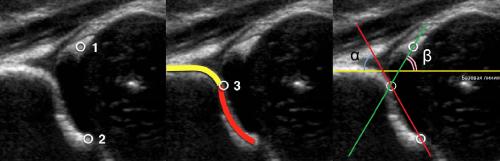

На первом этапе тазобедренный сустав сканируют в продольной плоскости. Проводят основные линии, измеряют костное покрытие головки, расстояние от лобковой кости до головки, ∠α и ∠β, а также определяют тип строения по Графу.

Датчик располагают в проекции большого вертела параллельно поясничному отделу позвоночника. Найдите самое глубокое место вертлужной впадины. Отрегулируйте наклон датчика, чтобы линия тела подвздошной кости лежала строго горизонтально (2).

Линии костной (красная) и хрящевой (зеленая) крыши проходят через костный выступ, а так же начало Y-хряща и центр гиперэхогенного кончика суставной губы, соответственно. Степень развития костной крыши определяет ∠α, а хрящевой крыши ∠β.

Если край подвздошной кости округлый, костный выступ определяют в точке перехода дуги наружного контура вертлужной впадины в дугу наружного контура подвздошной кости. Обратите внимание, все линии проходят по наружному контуру костей.

2d : 43°77°. Костная часть крыши уплощена. Костный выступ закруглен или плоский. Хрящевая крыша расширена. Заключение: Тяжелая дисплазия т/б сустава (тип 2d), предвывих (близко к децентрации головки). Гипсовая повязка на 3 недели, затем стремена Павлика. Контроль УЗИ 1 раз в месяц.

Тип 3 : ∠α

3a : Костная крыша и костный выступ плоские. Хрящевая крыша заворачивается кверху, эхоструктура однородная. Стойкая децентрация головки бедра. Заключение: Тяжелая дисплазия т/б сустава (тип 3а), подвывих. Закрытая репозиция, затем гипсовая повязка на 3 недели, далее стремена Павлика. Контроль УЗИ 1 раз в месяц.